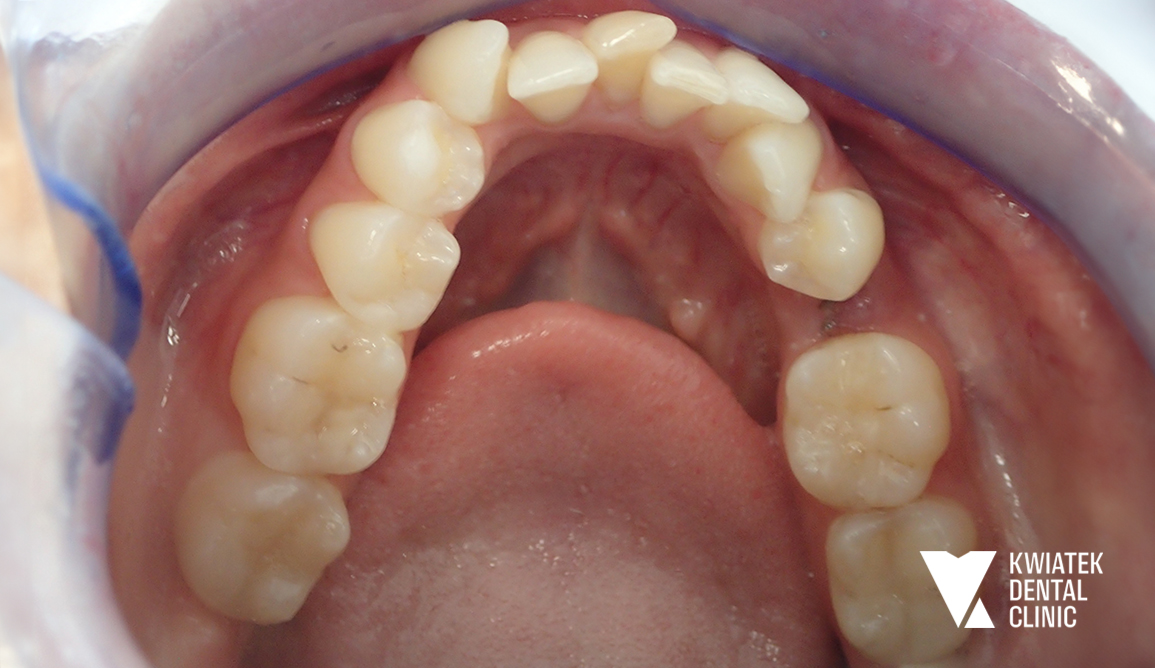

PRZED

Szczegółowa diagnostyka, obejmująca badanie kliniczne oraz zdjęcie panoramiczne, wykazała rozległe potrzeby lecznicze. Zidentyfikowano:

• liczne ubytki próchnicowe oraz nieszczelne wypełnienia

• konieczność leczenia kanałowego zębów 24 oraz 41

• obecność zębów zatrzymanych i korzeni wymagających ekstrakcji

• znaczne nagromadzenie kamienia nazębnego oraz niedostateczną higienę

• wyraźne stłoczenia zębów, szczególnie w łuku dolnym

• zaburzenia zgryzu oraz brak miejsca na odbudowy implantologiczne

Diagnostyka ortodontyczna potwierdziła dodatkowo przesunięcie linii pośrodkowej oraz niewystarczającą przestrzeń w łukach zębowych, co wymagało precyzyjnego planowania leczenia.